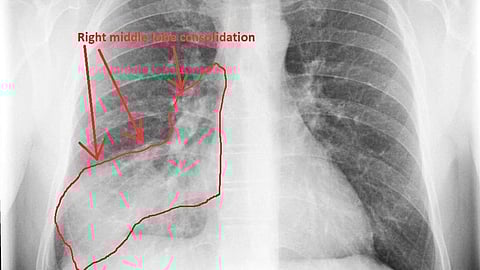

وأوضح النمر أن زيت الزيتون يمكن أن يتسرب إلى الرئتين مع التكرار، مما يسبب نوعًا من الالتهاب الرئوي يُعرف طبيًا باسم Pneumonitis Lipoid، وهو التهاب دهني يظهر بأعراض مثل الكحة، ضيق التنفس، وارتفاع الحرارة، وتُظهر الأشعة علامات واضحة لهذا الالتهاب.